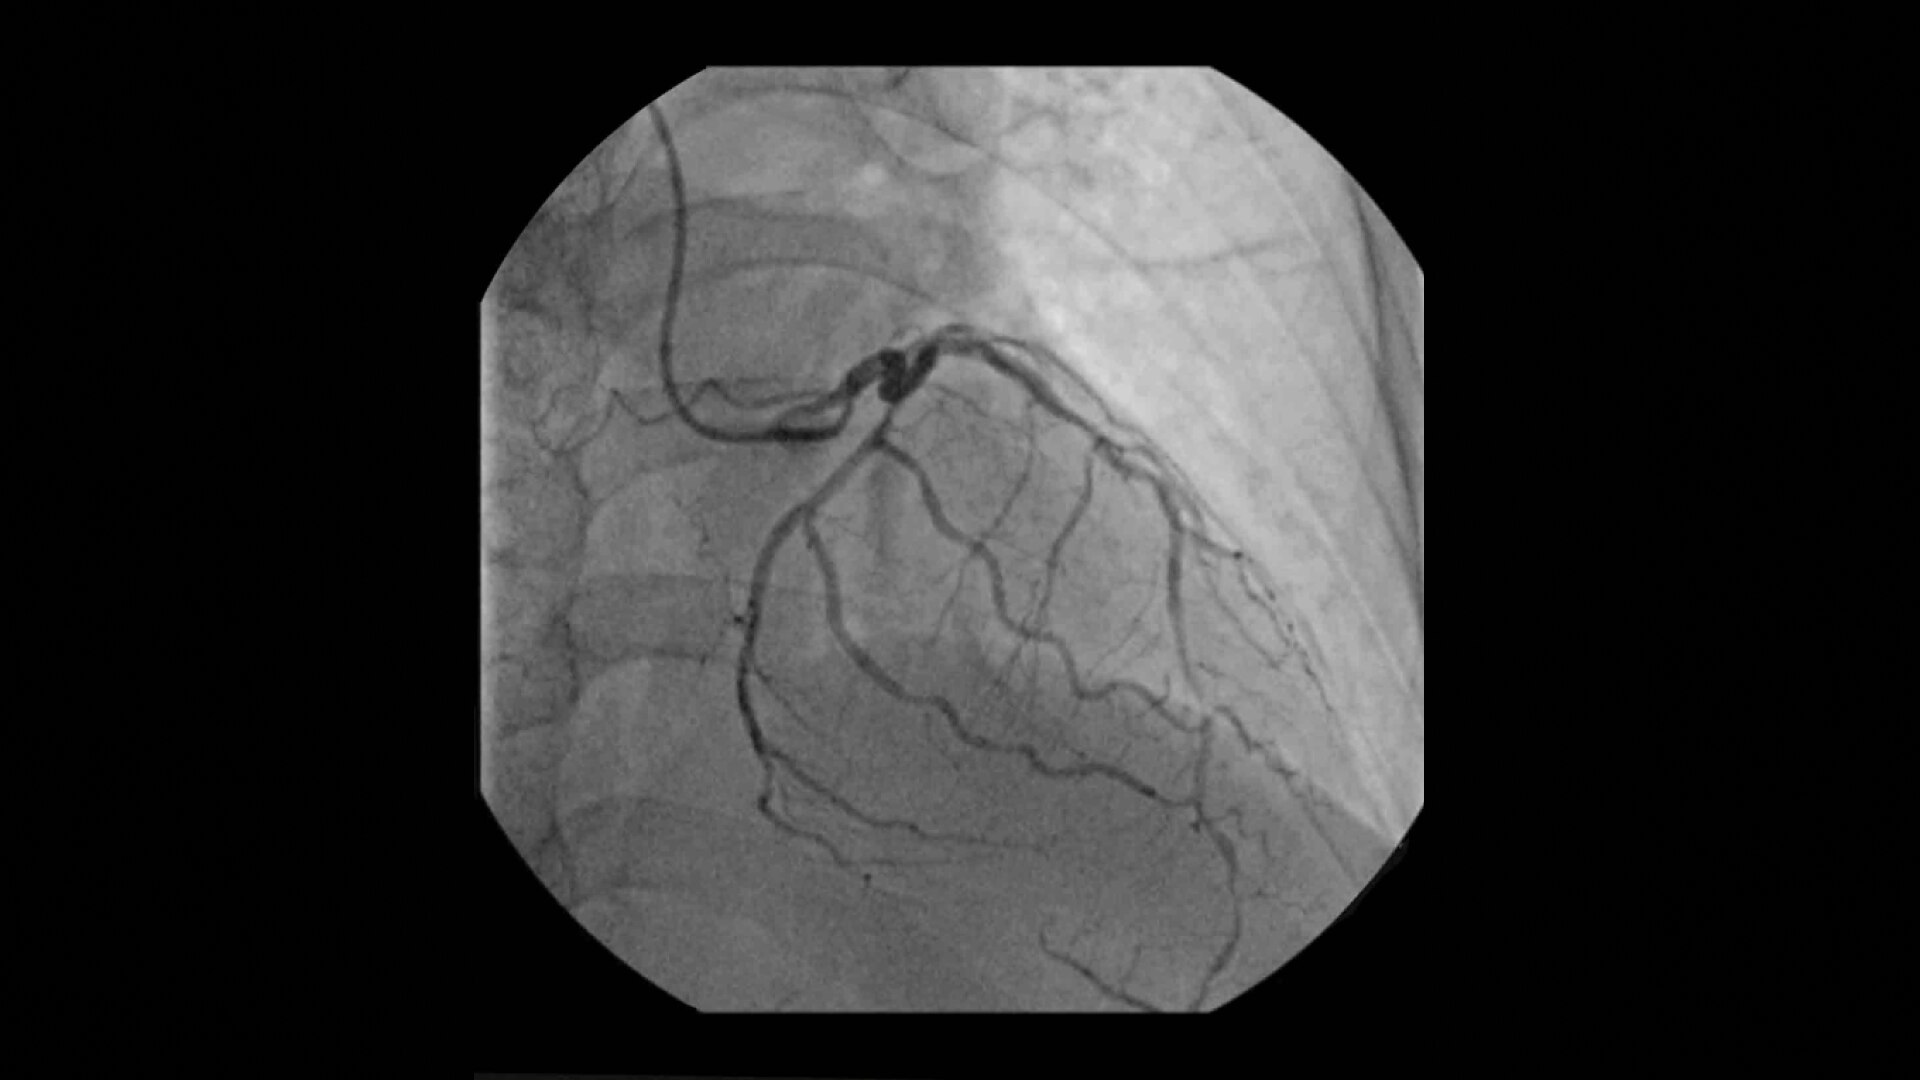

Achieve high-quality visualization necessary for complex cardiac procedures. OEC C-arms offer amazing image quality at low dose for efficient interventional imaging. Interventionalists and surgeons clearly see fine details of cardiac imaging, such as the border of the heart, leads, and small guidewires. Dynamic range management enables superb resolution, even with motion, during cardiac procedures.

See 0.014” guidewires in thoracic region or wire leads when placing biventricular pacemakers with the OEC Elite CFD flat detector, image processing, and 4K display.

Visualize moving interventional devices (catheters, stents) in vessels of the heart with the Cardiac Preset profile that automatically reduces blooming artifacts.

Cardiac imaging you need

Complex cardiac procedures require powerful imaging systems.

OEC premium C-arms perform a variety of procedures such as:

• Coronary artery diagnosis

• Percutaneous coronary intervention